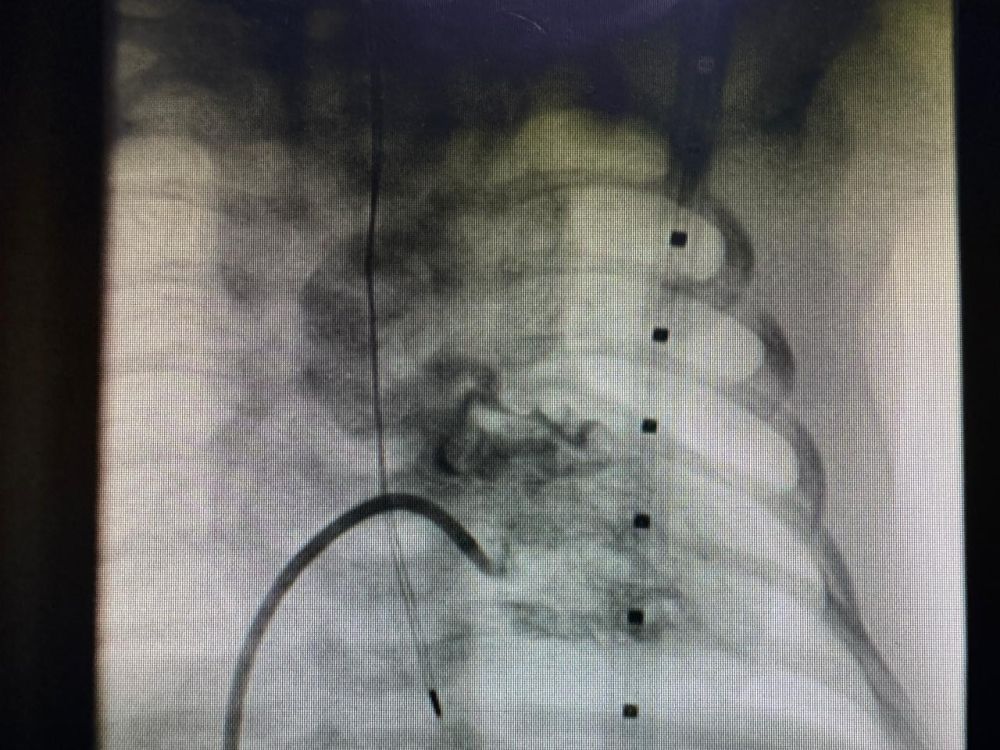

أشار التجمع أن الفريق الطبي قام بإجراء قسطرة قلبية تشخيصية وعلاجية بشكل عاجل، تضمنت زراعة دعامة شريانية لتوسعة الشريان الرئوي، في عملية استغرقت نحو 45 دقيقة وتكللت بالنجاح ولله الحمد، حيث ارتفعت نسبة الأكسجين لدى الطفل إلى ما بين 90-93%.

قسطرة تشخيصية وعلاجية

أشار التجمع أن الفريق الطبي قام بإجراء قسطرة قلبية تشخيصية وعلاجية بشكل عاجل، تضمنت زراعة دعامة شريانية لتوسعة الشريان الرئوي، في عملية استغرقت نحو 45 دقيقة وتكللت بالنجاح ولله الحمد، حيث ارتفعت نسبة الأكسجين لدى الطفل إلى ما بين 90-93%.